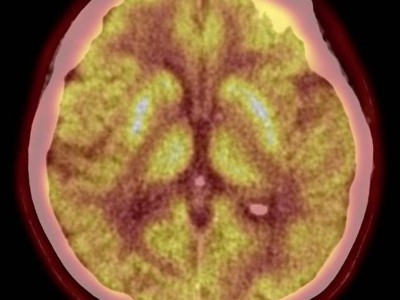

72-jährige Patientin mit erneuter Enzephalitis – gleiche Antikörper, neue Fragen

Eineinhalb Jahre nach Diagnose einer GAD-assoziierten Enzephalitis wird die 72-Jährige erneut wegen progredienter neurologischer Beschwerden aufgenommen. Wie wichtig eine interdisziplinäre Diagnostik ist und welche Rolle die Glukosewerte in diesem Fall haben, wird im folgenden Fallbeispiel beschrieben.

Junger Mann trinkt Wasser/© Syda Productions / stock.adobe.com (Symbolbild mit Fotomodell), Frau hält Tablette an den Mund/© fizkes / stock.adobe.com (Symbolbild mit Fotomodell), Zwei Injektionspens mit Semaglutid/© Kassandra / Stock.adobe.com, Ärztin erklärt adipösem Mann Testergebnisse/© Halfpoint / Stock.adobe.com (Symbolbild mit Fotomodell), Junge Frau bei Ophthalmoskopie/© Daniel Balakov / Getty Images / iStock (Symbolbild mit Fotomodell), Hand an einer Lampe im Operationssaal/© karrastock / Stock.adobe.com, Galenus-von-Pergamon-Preis 2025 in der Kategorie Primary Care /© Marc-Steffen Unger, EKG bei einer Frau/© Staras / Getty Images / iStock (Symbolbild mit Fotomodell), Hand hält Injektionspen/© millaf / Stock.adobe.com (Symbolbild mit Fotomodell), Setzen eines Magenbypasses/© Herjua / stock.adobe.com (Symbolbild mit Fotomodellen), Senior hält Tabletten und Glas Wasser in den Händen/© Andrii Zastrozhnov / Stock.adobe.com (Symbolbild mit Fotomodell), Seniorin setzt sich Bauchspritze/© Halfpoint / stock.adobe.com (Symbolbild mit Fotomodell), FDG-PET bei 72-jähriger Patientin: pathologischer Hypermetabolismus der Putamina beidseits/© Kellner C et al. / all rights reserved Springer Medizin Verlag GmbH, Blut wird abgenommen/© Chutipon / Stock.adobe.com (Symbolbild mit Fotomodell), Search Icon, Die Leitlinien für Ärztinnen und Ärzte, Stereotaktische Strahlentherapie (SBRT) einer solitären ossären Metastase in dem Brustwirbelkörper/© Springer Medizin Verlag GmbH, Hirntumoren sichtbar im MRT/© semnic / Getty Images / iStock (Symbolbild mit Fotomodell), Endobronchialer Befund mit exophytischem Tumor im Bereich des rechten Oberlappens/© Möller, M., Schütte, W. / all rights reserved Springer Medizin Verlag GmbH, Aufziehen einer Spritze/© Eisenhans / Fotolia